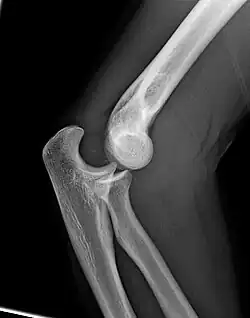

Left: Lateral X ray of a dislocated right elbow

Right: AP X ray of a dislocated right elbow

Dislocation

X-ray of ventral dislocation of the radial head. There is calcification of annular ligament, which can be seen as early as 2 weeks after injury.[29]

Elbow dislocations constitute 10% to 25% of all injuries to the elbow. The elbow is one of the most commonly dislocated joints in the body, with an average annual incidence of acute dislocation of 6 per 100,000 persons.[30] Among injuries to the upper extremity, dislocation of the elbow is second only to a dislocated shoulder. A full dislocation of the elbow will require expert medical attention to re-align, and recovery can take approximately 6 weeks.